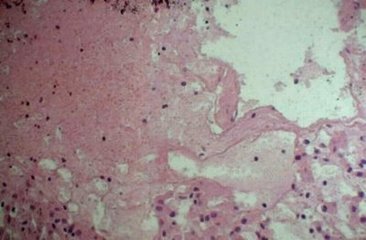

家族性地中海热